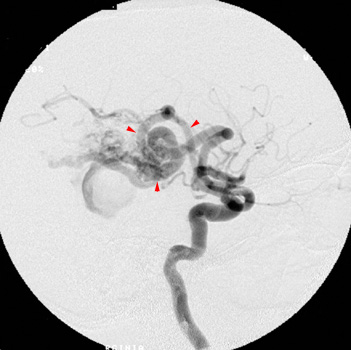

Head CT > Stroke > Hemorrhage Due to AM

Hemorrhage Due to Arteriovenous Malformation

An underlying arteriovenous malformation (AVM) may or may not be visible on a CT scan. However, prominent vessels adjacent to the hematoma suggest an underlying arteriovenous malformation. In addition, some arteriovenous malformations contain dysplastic areas of calcification and may be visible as serpentine enhancing structures after contrast administration.